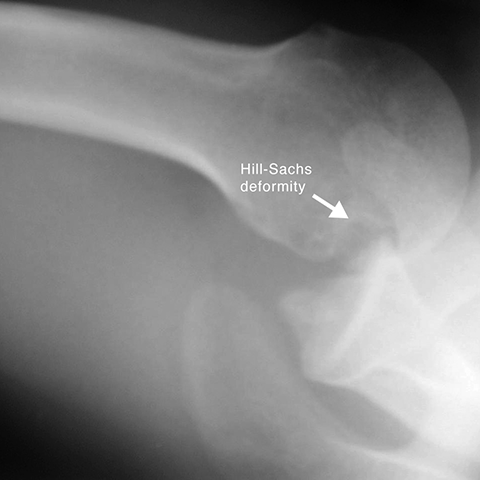

Hill-Sachs fracture